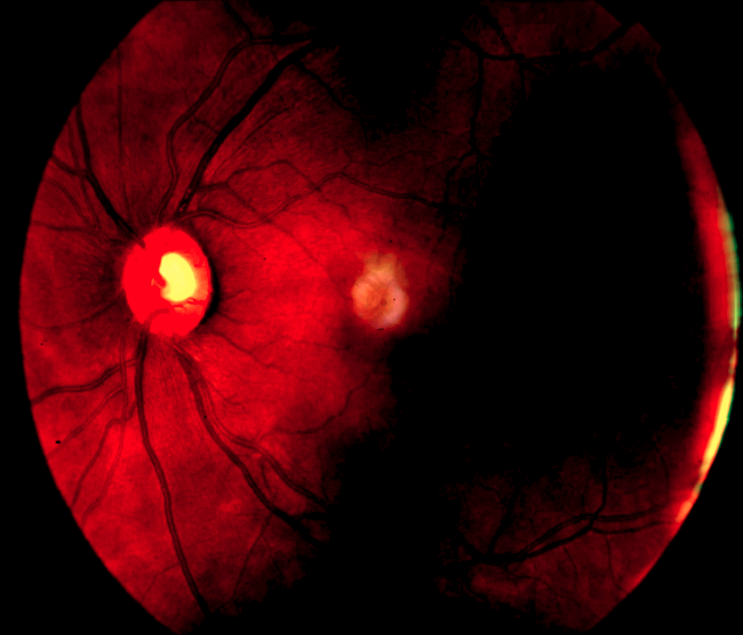

4.2.2 Dataset

The Brazilian Multilabel Ophthalmological Dataset (BRSET) [23] includes 2D color fundus retinal photos (see Fig.˜2(a)) as well as patient specific data in tabular form as presented in Table˜2. The authors provide 16,266 image–tabular data-pairs from 8,524 patients. The 14 target classes can be used for multimodal disease classification. The classes include 13 diseases (i.e. diabetic retinopathy, macular edema, scar, nevus, amd, vascular occlusion, hypertensive retinopathy, drusens, hemorrhage, retinal detachment, myoptic fundus, increased cup disc, other) and one class indicating no finding.